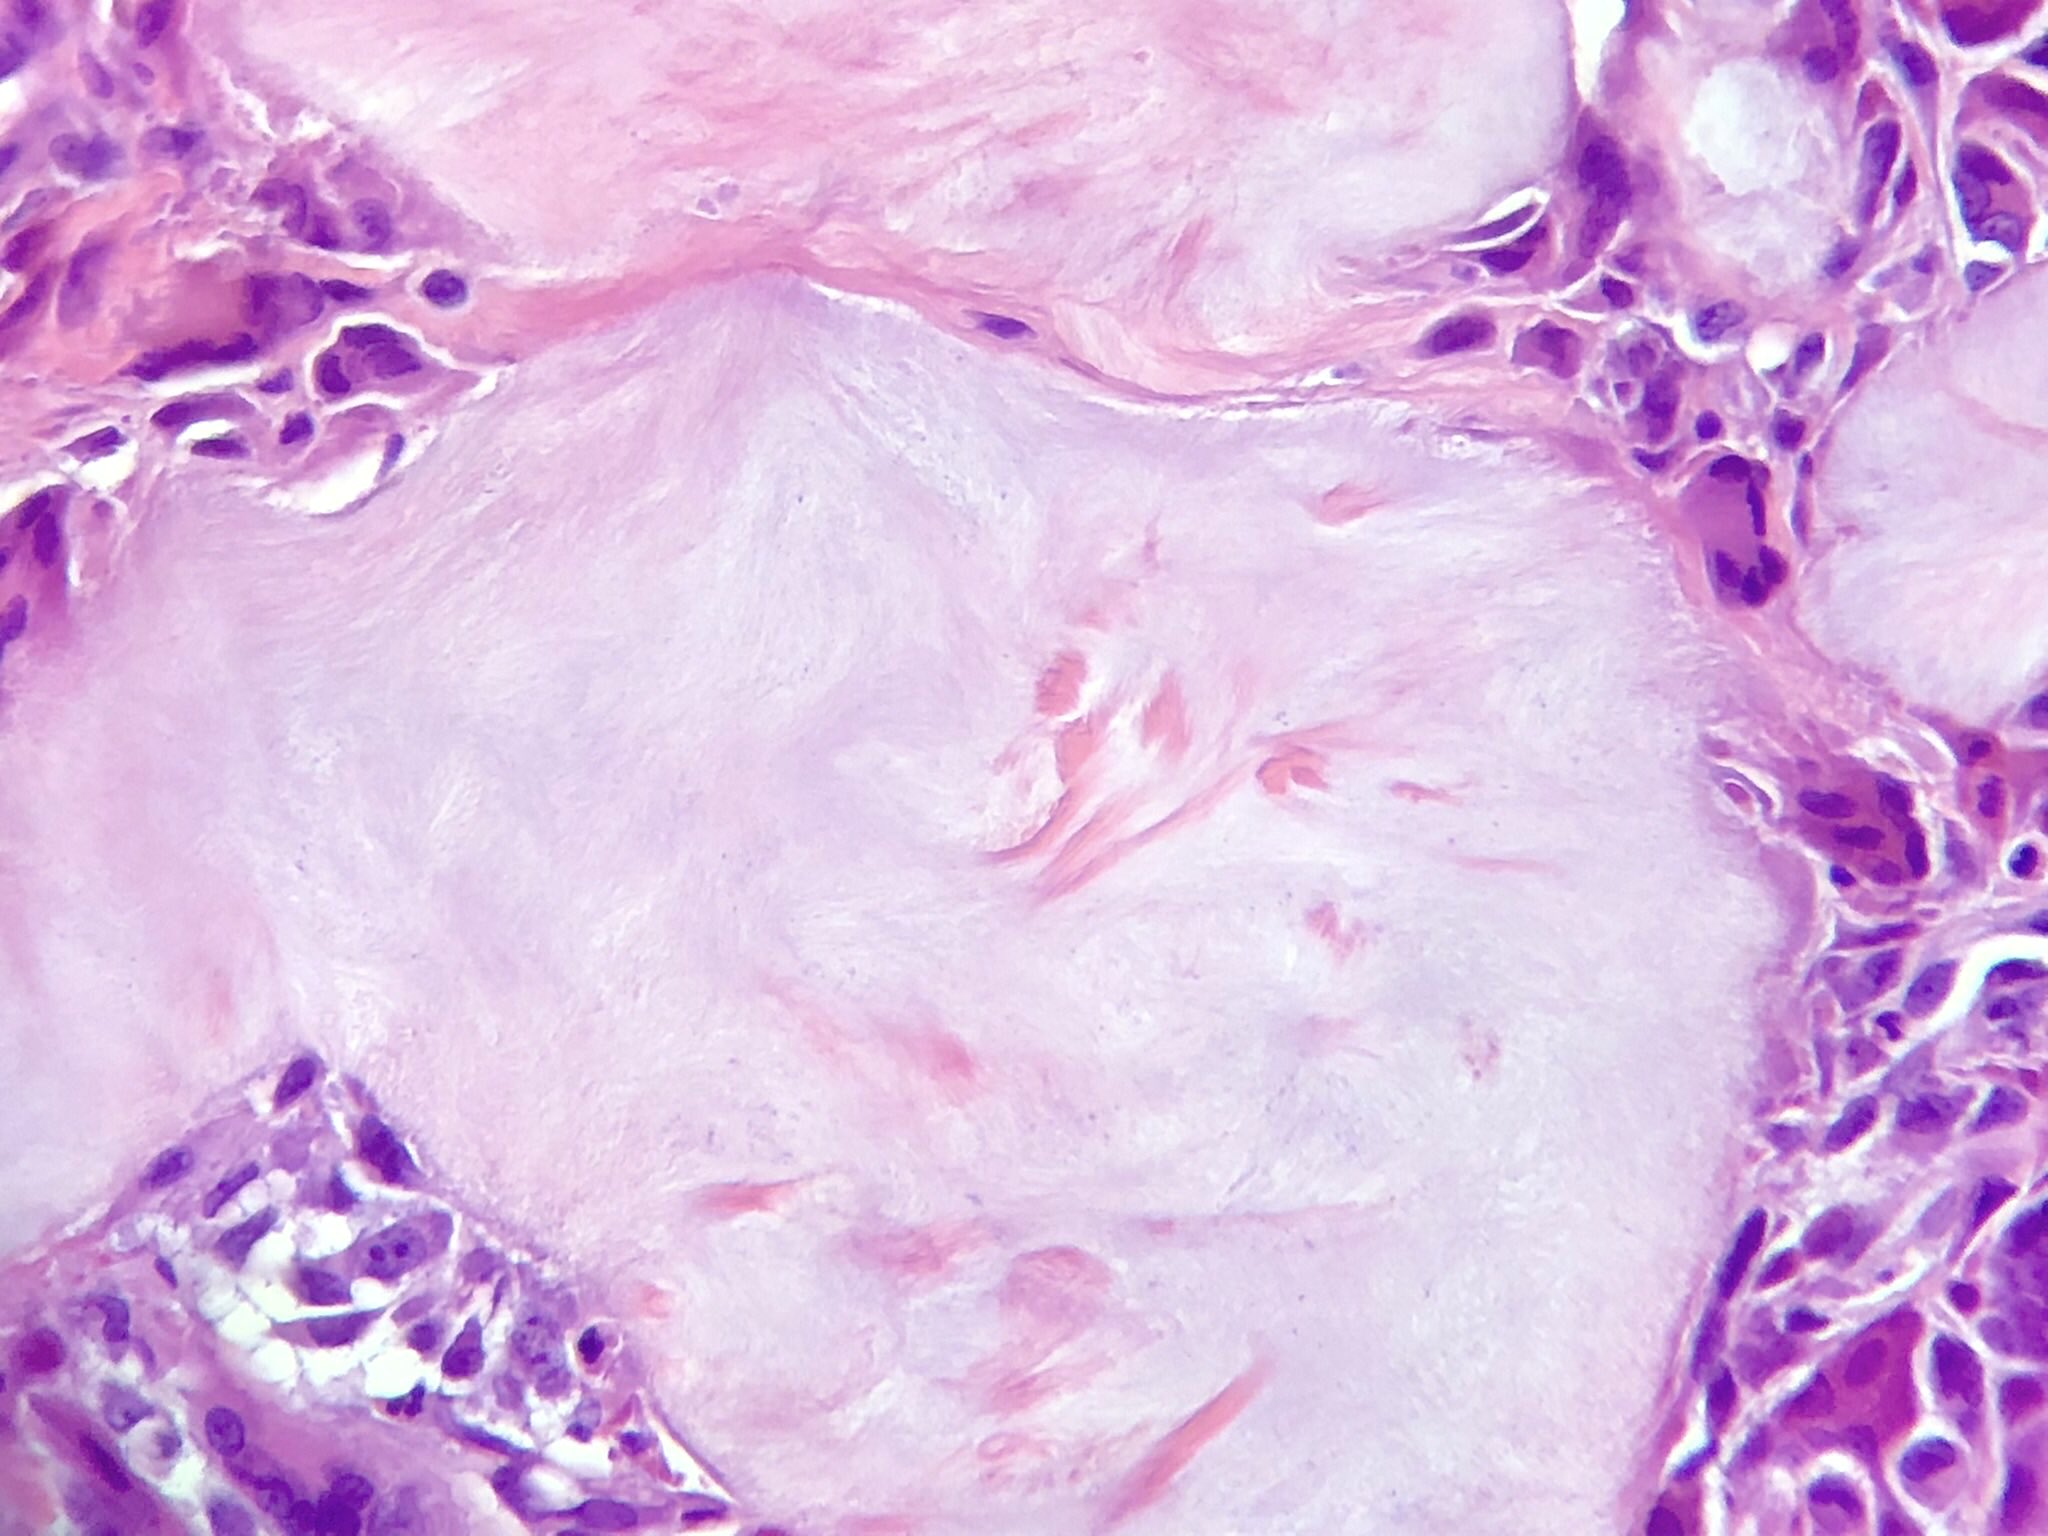

Microscopic (histologic) description

- Gout tophus:

- Nodular aggregates / granuloma-like appearance consisting of acellular, amorphous, pale eosinophilic material surrounded by palisading arrangement of histiocytes and multinucleated giant cells (Dermatol Online J 2015;21:13030)

- Feathery appearance in some deposits due to empty needle shaped spaces (Skeletal Radiol 2020;49:1325)

- Presence of monosodium urate crystals (MSU) is diagnostic

- Needle-like crystals that measure 5 - 25 micrometers in length

Microscopic (histologic) images